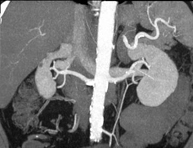

Diagnostic test that involves obtaining high-definition anatomical two- and three-dimensional images of the kidney and urinary system using CT (computed tomography) equipment. The study is performed before and after the use of iodinated contrast in different ‘renal phases’ for functional and anatomical assessment (renal parenchyma, ureters, urinary bladder, renal arteries and veins, etc.), as well as adjacent structures (inferior vena cava, abdominal aorta, liver, spleen, etc.). It is particularly recommended when kidney damage is suspected, in patients with blood in their urine or haematuria, etc.

- Renal artery CT angiography

A non-invasive diagnostic test that involves studying the renal arteries by obtaining high-definition anatomical images using CT (computed tomography) equipment and iodinated contrast. With the aid of workstations specialised for arterial studies, the image quality supports 2D and 3D reconstructions. This test is recommended, for example, in patients suffering from refractory hypertension that does not respond to processing, in patients with kidney damage in order to obtain a pre-surgical ‘vascular’ map, etc.